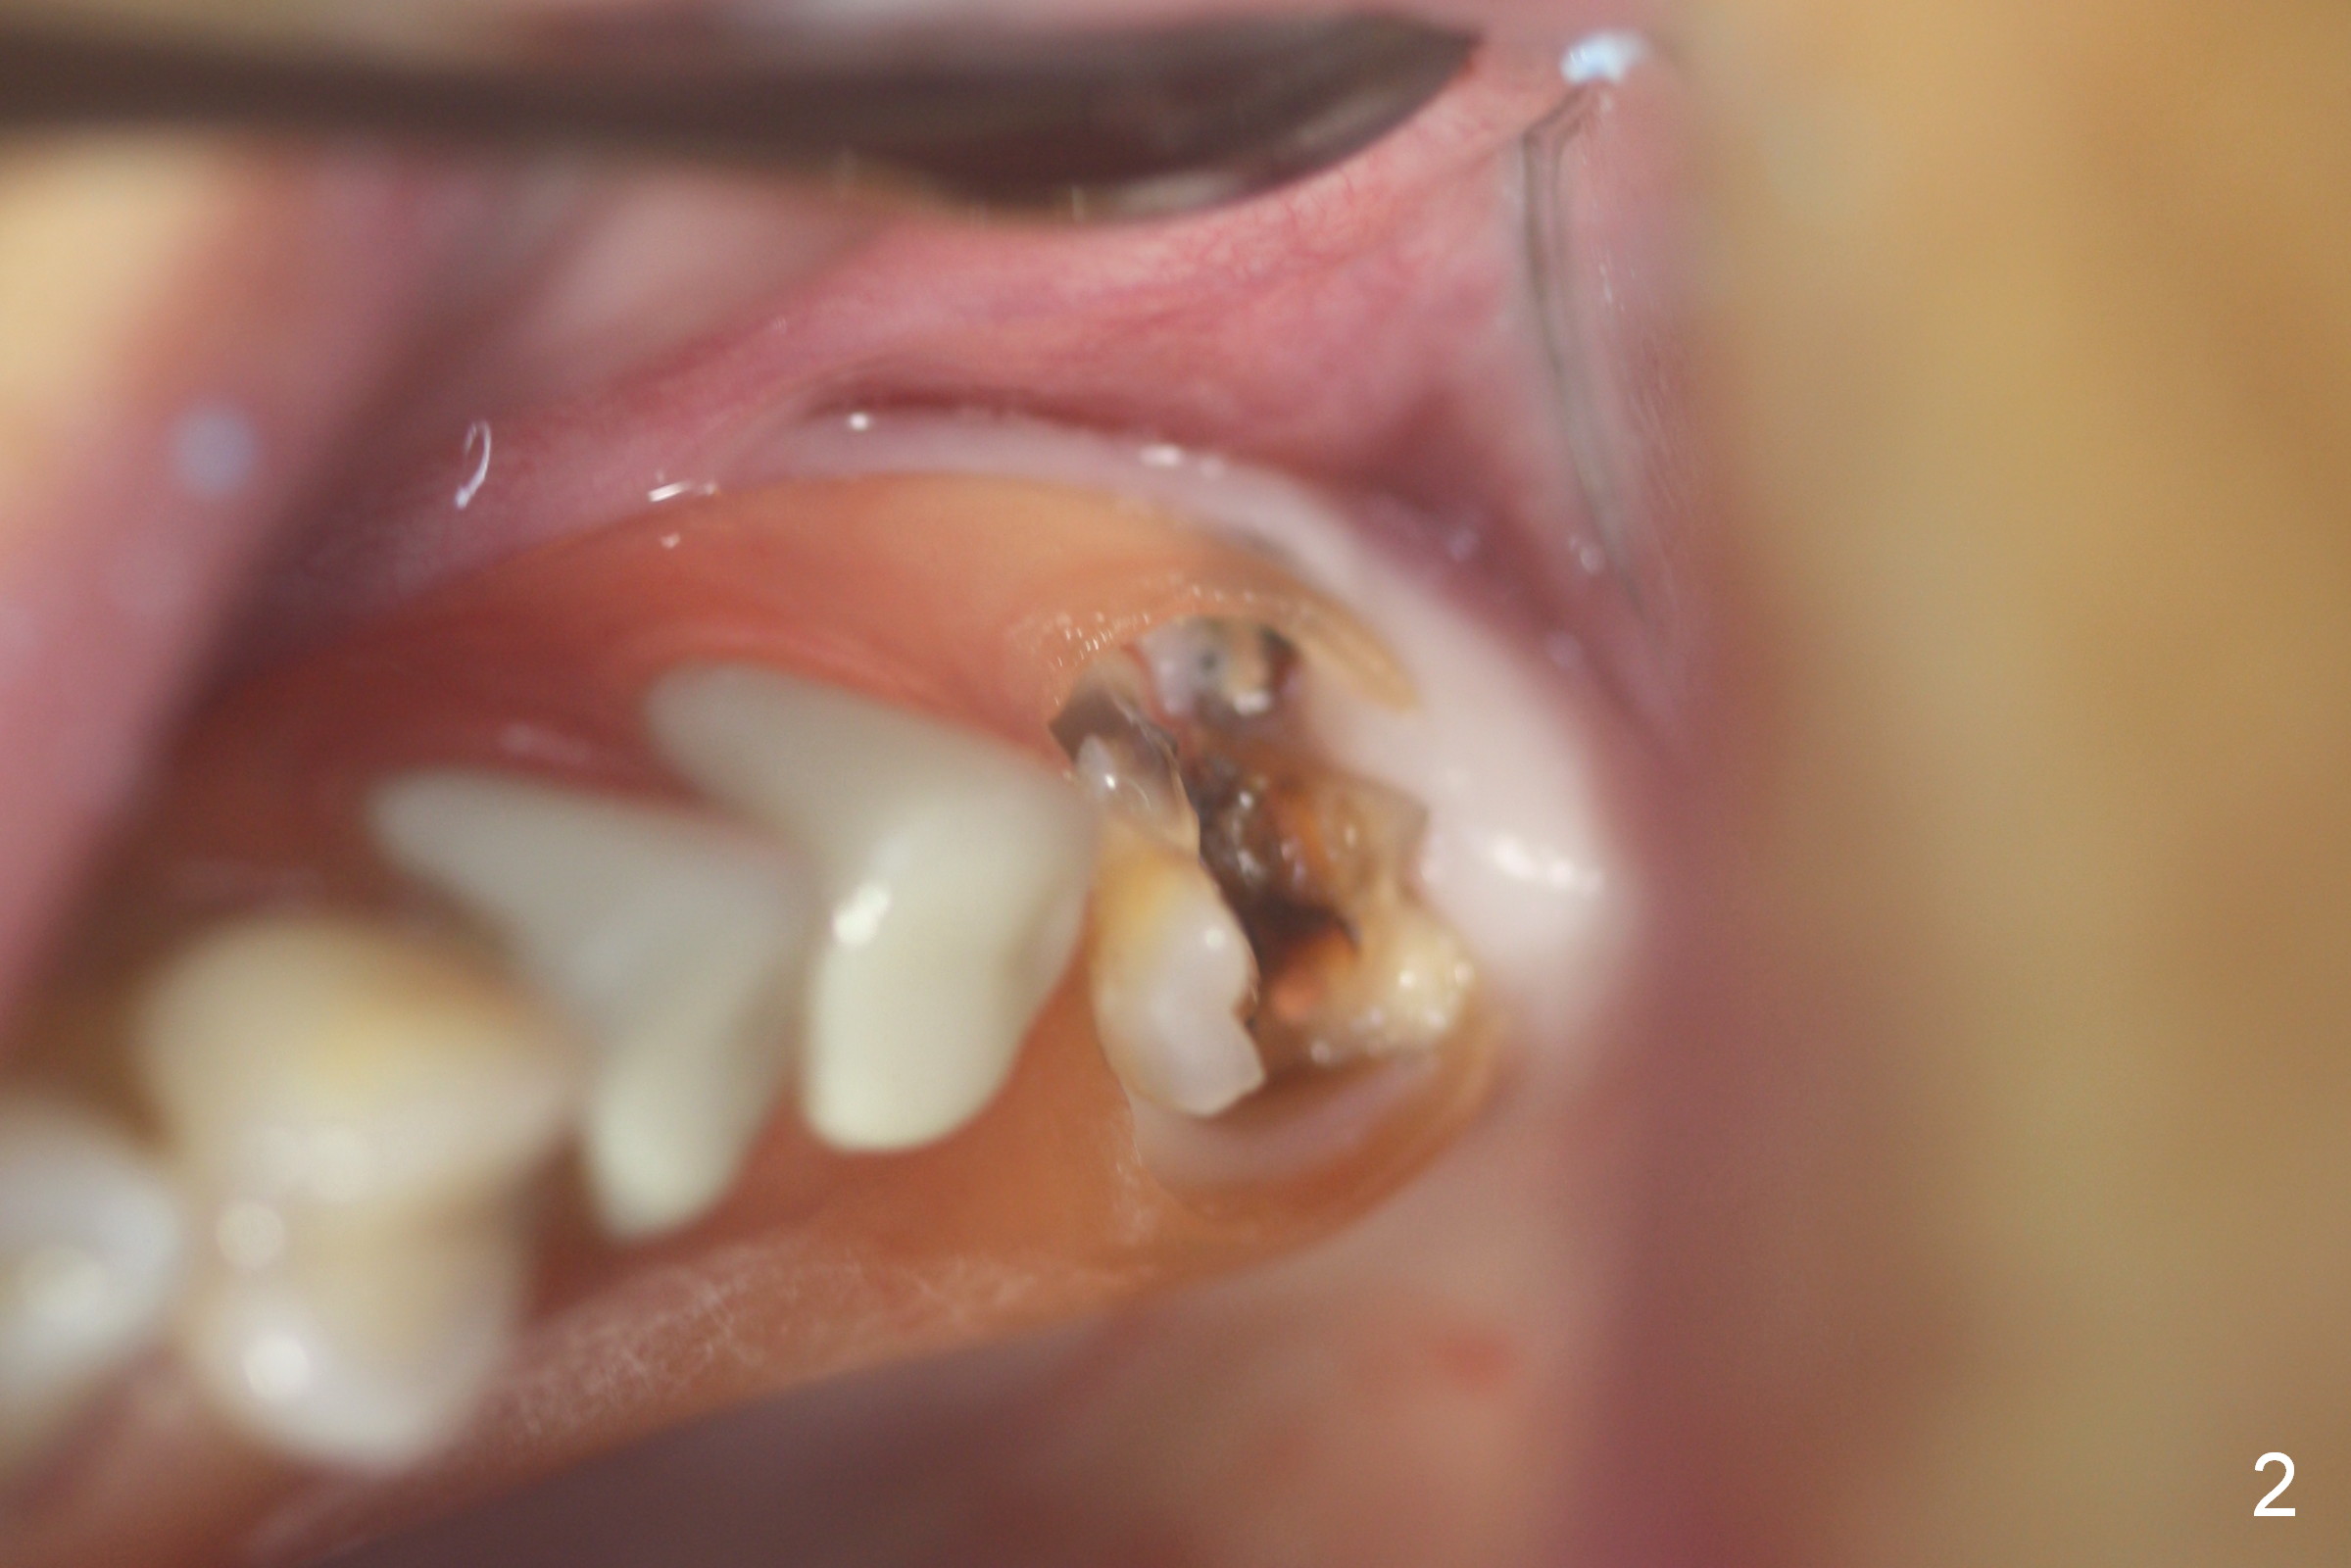

Fig.1,2 show the close relationship of the upper flipper and the residual roots at #15. Atraumatic extraction using periotomes and surgical sectioning still results in perforation of the mesiobuccal socket (Fig.3 >). The distobuccal one is shallow, while the septum is small. It appears that the palatal (Fig.3 P) socket is the most ideal recipient site for the immediate implant and is expanded with Magic Osteotomes until 4.3 mm (Fig.4,5) with the coronal end pushed as buccal as possible. After placing allograft for sinus lift (Fig.6 >), a 5x11 mm IBS implant is placed with insertion torque ~ 50 Ncm. A 6x4(3) mm pair abutment is placed, followed by bone graft in the remaining sockets (Fig.6 *) and by Osteogen plug (Fig.7 *). Finally the socket is sealed by applying acrylic over the abutment (Fig.8). While the acrylic is setting, the flipper is seated and excess acrylic is removed and pushed away from the flipper (Fig.9). Advise the patient not to wear the flipper. If it is being worn, there will be minimal contact between the flipper and the immediate provisional.